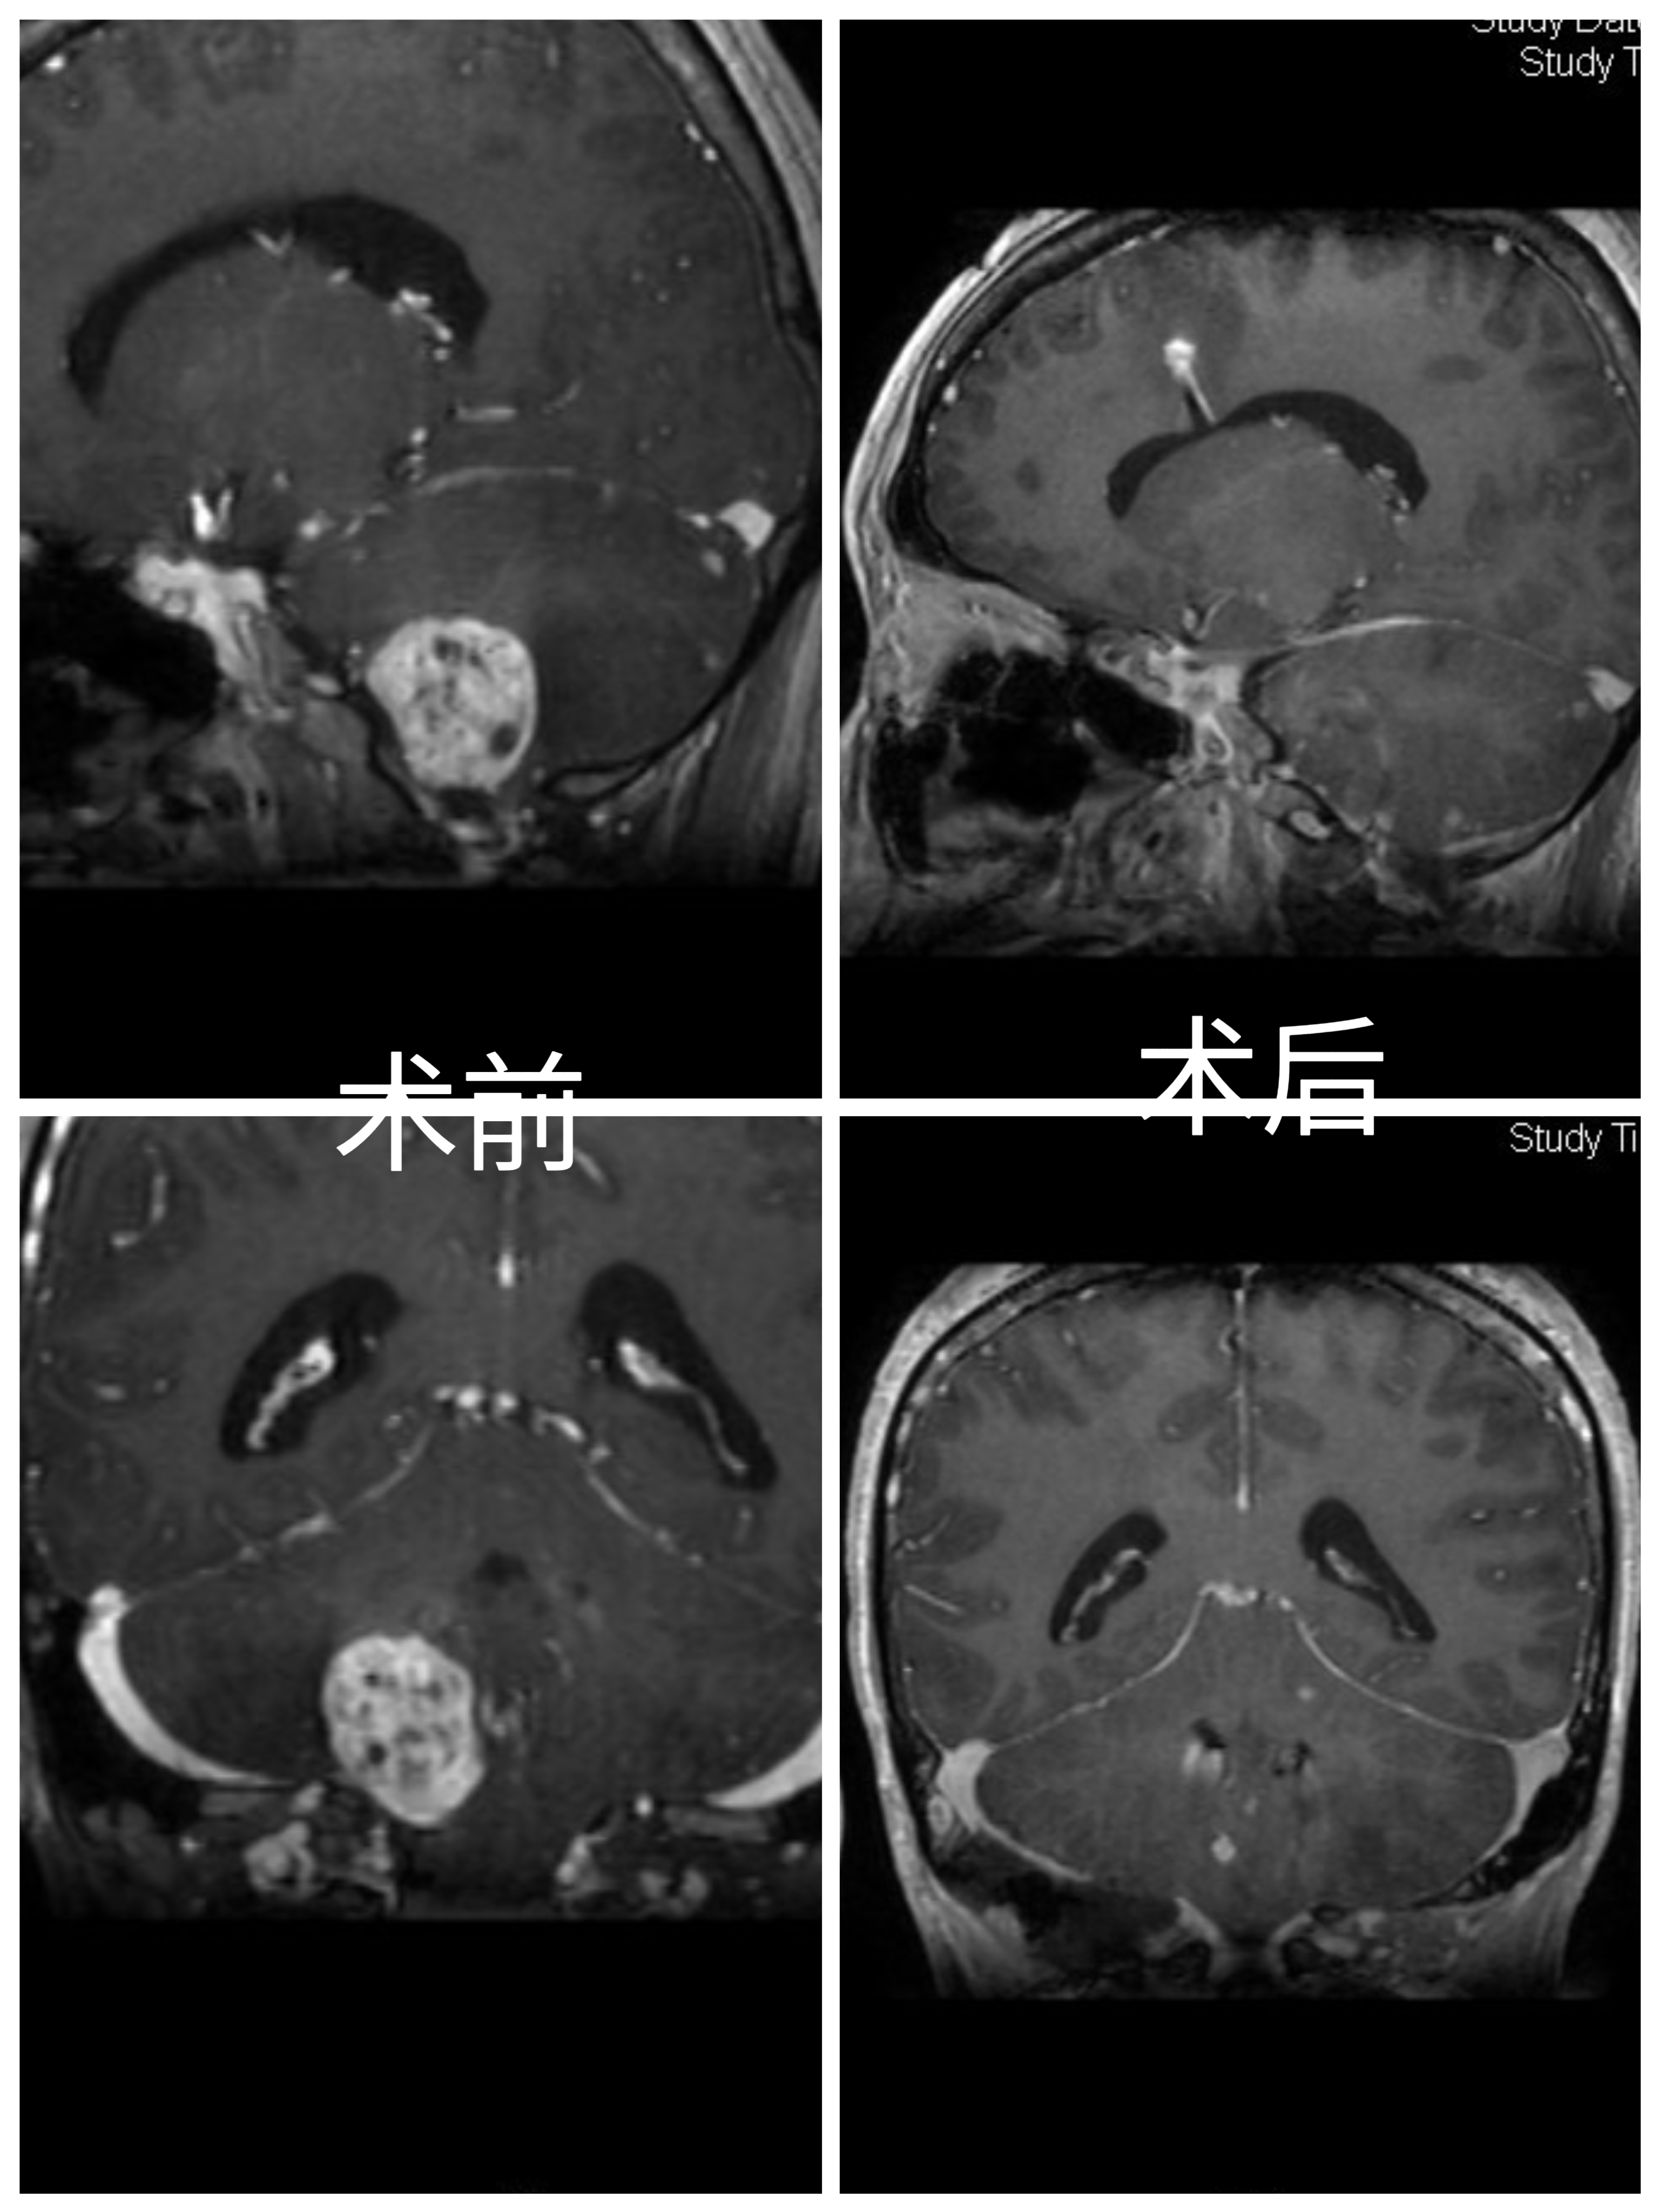

手术要点:

1.开颅前侧脑室外引流。

2.乳突后切口,延长至寰椎水平。

3.骨窗显露乙状窦,打开枕大孔外侧缘。

4.在小脑半球及小脑扁桃体外侧,切开脑组织,即见红色肿瘤。

5.沿肿瘤边缘分离,电凝切断血供,保护粗大引流静脉。

6.术中见肿瘤供血动脉,主要来源于小脑后下动脉的延髓外侧段、延髓近四脑室侧孔处动脉。

7.弱电凝延髓外侧细小血管,保护延髓正常血管。

8.临时阻断PICA,肿瘤血供明显减少。因肿瘤位于狭小空间,整体切除容易造成延髓损伤,而且不易电凝供血动脉。分块切除肿瘤,电凝切断延髓外侧段PICA,同时保护延髓及PICA。

9.严格沿边缘切除肿瘤,延髓表面静脉压迫止血。

10.术后病人轻度声音嘶哑、饮水呛咳。肢体活动正常。

Surgical points:

1. Preoperative external ventricular drainage on the lateral side of the brain.

2. mastoid incision, extended to the level of the atlas.

3. expose the sigmoid sinus through the bone window, and open the lateral edge of the foramen magnum.

4. On the lateral side of the cerebellar hemisphere and cerebellar tonsil, cut the brain tissue to reveal the tumor.

5. Separate along the edge of the tumor, coagulate and cut off the blood supply, and protect the large drainage veins.

6. During the operation, it was found that the feeding arteries of the tumor mainly originated from the lateral segment of the PICA ,near the foramen of the fourth ventricle of the medulla oblongata.

7. Weak coagulation of the small vessels on the lateral side of the medulla oblongata to protect the normal vessels of the medulla oblongata.

8. Temporarily block the PICA, and the blood supply of the tumor is significantly reduced. Due to the tumor located in a narrow space, it is difficult to remove the tumor as a whole ,and it is easy to damage the medulla oblongata. The tumor is removed in pieces, and the PICA on the lateral segment of the medulla oblongata is coagulated and cut off while protecting the medulla oblongata and PICA.

9. Strictly remove the tumor along the edge, and compress and stop bleeding on the surface of the medulla oblongata.

10. After the operation, the patient had mild hoarseness and drinking choking. The limb activity was normal.